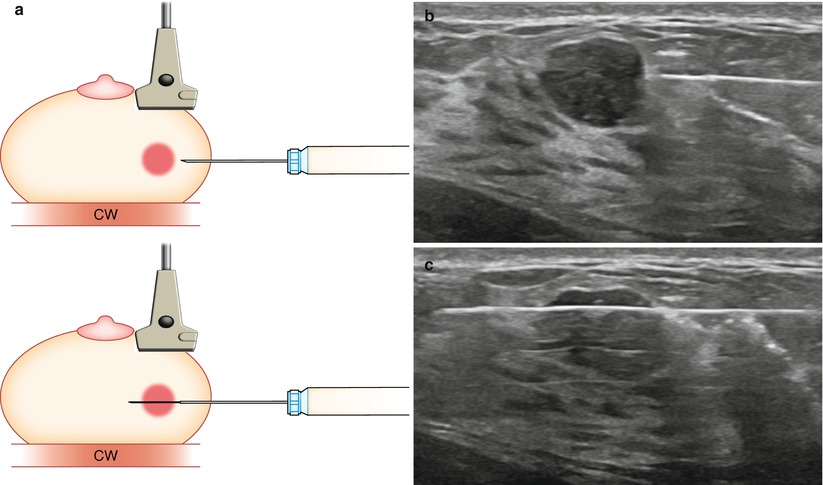

Preethi underwent a mammogram and breast ultrasound. The imaging showed a suspicious lesion. Hence we decided to get a core needle biopsy.